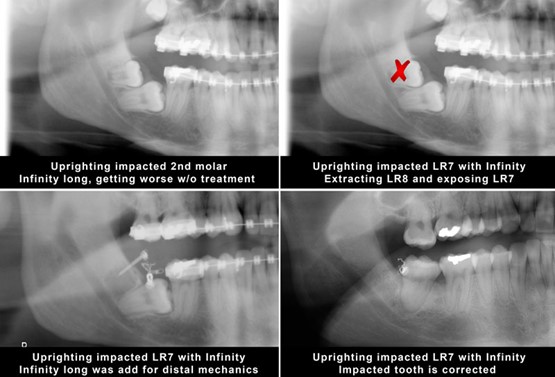

5. Upright mesially tilted second molas as well as third molars if needed.

You can place the infinity Temporary Anchorage Device TADs mesial or distal to upright the tilted tooth.

a. If you place the mini implant mesially, then you need a cantilever system to deliver the uprighting force as the case below

b. If you place the mini implant distally, then you need to use a power chain or a closed coil NiTi to deliver the upright force.